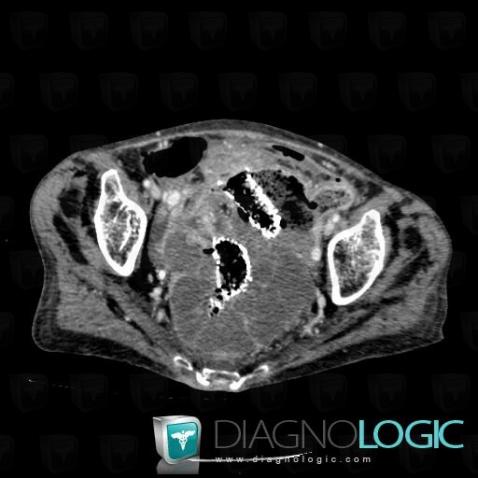

Sigmoid cancer, Colon, CT

Here is the specific information in the key image above:

- Diagnosis Sigmoid cancer (link to Colon cancer), Location(s) Colon, with gamuts Colonic mass or filling defect, Thickening of colon wall, Marked thickening of colon wall, Colonic stenosis